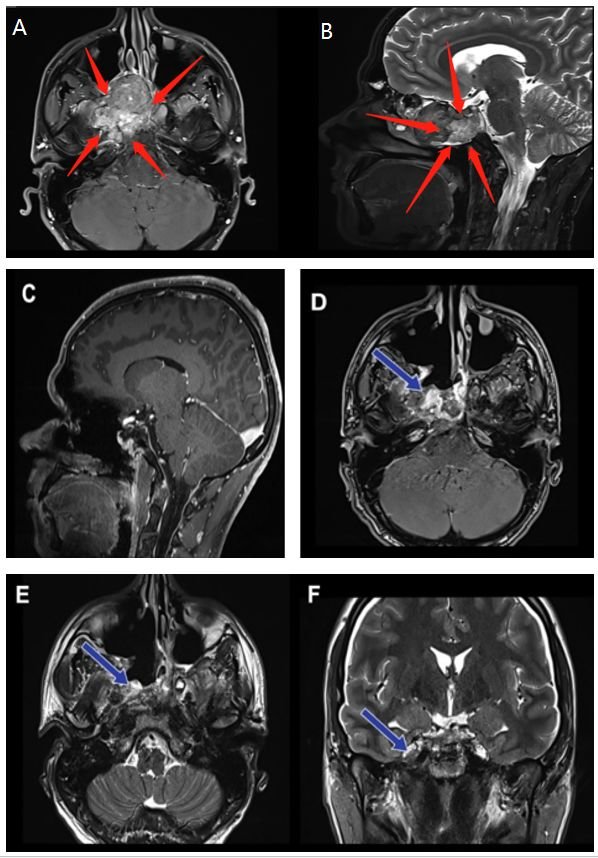

术前(红色箭头):A、B图显示位于右海绵窦中心的脊索瘤病变。病变集中在右侧海绵窦和翼骨上,并在右侧邻卵圆孔。

术后(蓝色箭头):C图表示矢状位显示无肿瘤残余。D、E、F图显示轴位、冠状位脊索瘤被绝大部分切除。